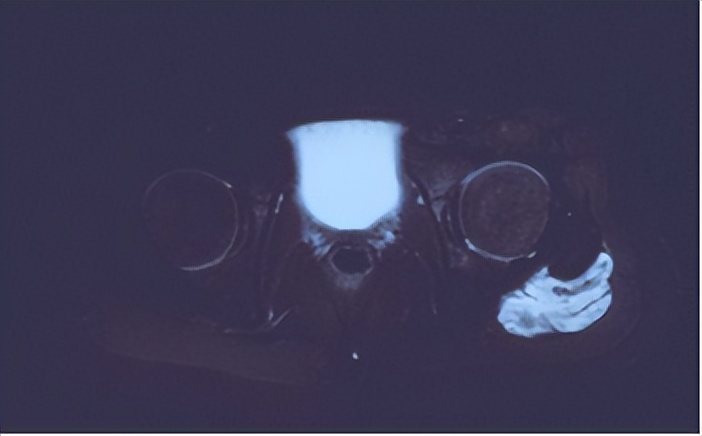

患儿家长近期发现孩子说左侧屁股疼痛,肉眼可见左侧臀部肿胀,鼓包。家长先后就诊于多家医院行超声,X线等检查,超声提示左臀部髋关节后方肌层内低回声肿物,考虑血管瘤。核磁检查提示左髋后侧股方肌见不规则团块状占位性病变,大小约39*25*48mm。考虑血管瘤?通过网上查询,发现我院在血管瘤和脉管畸形治疗方面很有经验。遂来到我门诊看病。在看过病人后,结合超声,MRI以及化验检查,考虑患儿应该是左臀部的静脉畸形。这种低流速的血管畸形表现为静脉扩张或局部海绵状肿块,涉及多个组织和器官。在早晨起床、寒冷天气或长时间运动时出现疼痛。当合并局限性凝血功能异常时,则表现为更明显、更持久的疼痛,并伴有明显的肿胀和异常感觉。立即安排了相关术前检查,并抓紧安排住院治疗。

MRI提示 血管畸形